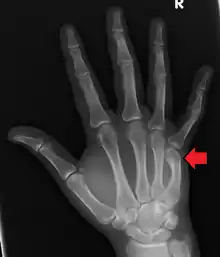

| Boxer's fracture of the 5th metacarpal head from punching a wall | |

A boxer's fracture is the break of the 5th metacarpal bones of the hand near the knuckle.[4] Occasionally it is used to refer to fractures of the 4th metacarpal as well.[1] Symptoms include pain and a depressed knuckle.[2]

Classically, it occurs after a person hits an object with a closed fist.[3] The knuckle is then bent towards the palm of the hand.[3] Diagnosis is generally suspected based on symptoms and confirmed with X-rays.[3]